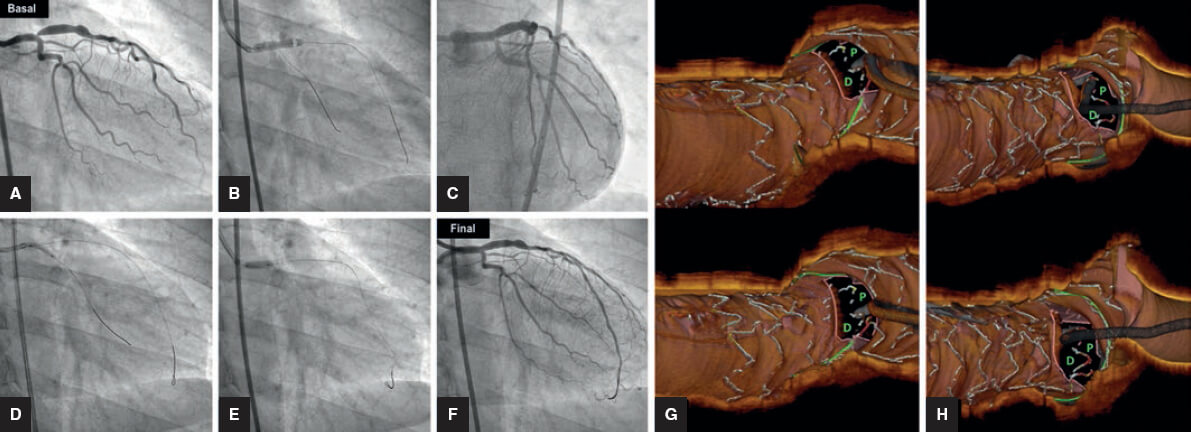

En la valoración pretratamiento, la tomografía de coherencia óptica proporciona una información similar a la de la IVUS, con las ventajas y los inconvenientes mencionados. Donde verdaderamente ha supuesto una revolución ha sido en la visualización de los struts del stent. La resolución con que los identifica, junto con la utilización de nuevo software, permiten una reconstrucción del stent muy similar a la que se obtiene en los estudios in vitro. Resulta una técnica muy sensible para identificar deformaciones, no aposiciones y no expansiones. Al mismo tiempo, proporciona información precisa sobre las relaciones del vaso con el stent, en especial entre las celdillas y el origen de la RL. Para establecer esta relación, es la única técnica disponible. Así, permite el diagnóstico del acceso a la RL a través de la celdilla proximal o distal. La recomendación, a partir de los estudios in vitro, es acceder a través de la celdilla distal, con lo que se consigue un mejor andamiaje de la rama y una menor deformidad del stent del VP. La monitorización con tomografía de coherencia óptica del procedimiento permite identificar un acceso proximal y corregirlo por uno más distal (figura 7). La utilidad de esta técnica en el tratamiento de las bifurcaciones ha sido resumida en un documento de consenso del European Bifurcation Club49.

Figura 7. Tratamiento de una lesión ostial de la descendente anterior con la técnica del stent provisional. A: angiografía basal. B: stent en tronco/descendente anterior. C: compromiso del origen de la arteria circunfleja. D: dilatación de la circunfleja. E: redilatación proximal (Re-POT). F: resultado angiográfico. G: tomografía de coherencia óptica, wiring incorrecto de la circunfleja a través de la celdilla proximal (P). H: tomografía de coherencia óptica en la que tras un segundo intento la guía aparece a través de la celdilla distal (D), donde finalmente se efectúa la dilatación.